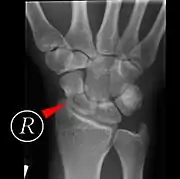

Scaphoid fractures may be difficult to diagnose via plain x-ray, so repeat x-ray may be used at a later date, or cross-sectional imaging via MRI or CT scan.[5]